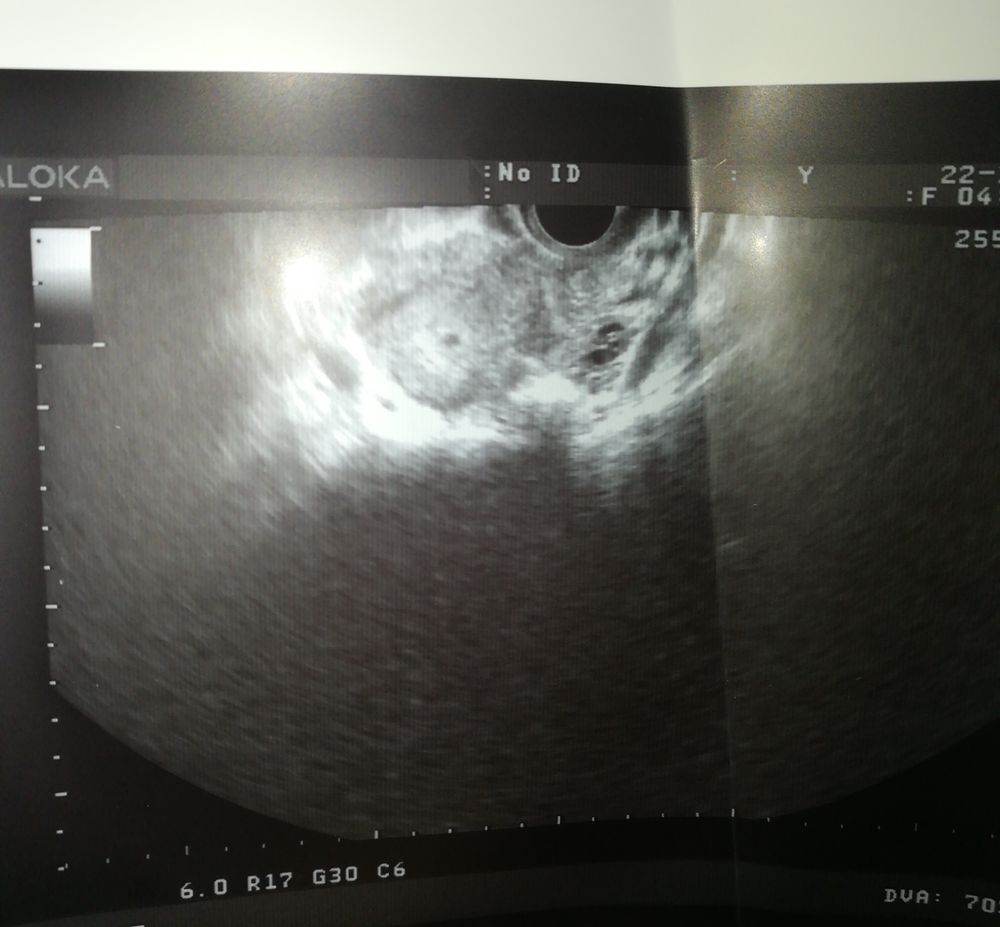

Гляньте пожалуйста узи

Это вена/сосуд

Может быть это желтое тело в яичнике?

Я думаю -то, что справа

Справа скорее всего яичники)

Я наоборот думаю,то что справа -плодное яйцо